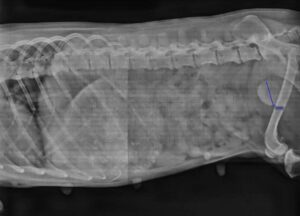

Kalytė gyveno Gilvyčiuose pririšta prie būdos neprižiūrima – suvargusi, alkstanti, blūsėta. Po vet. apžiūros rastas šl. pūslėj 3 cm skersmens akmuo, laukia operacija. Tel. 067612231